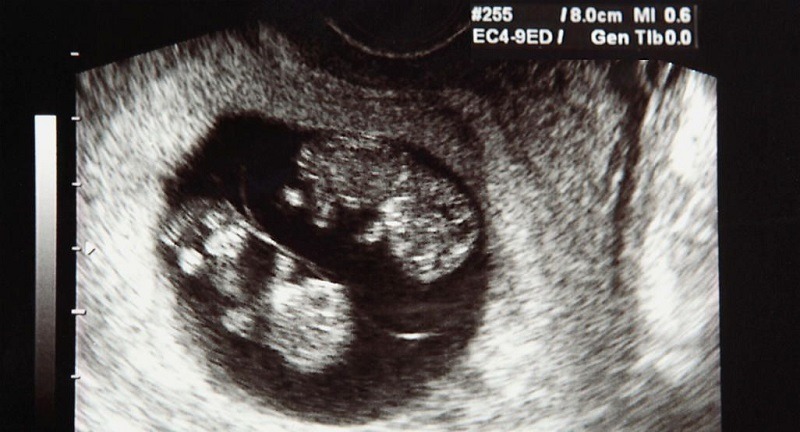

Siêu âm hoàn toàn có thể phát hiện thai đôi và là phương pháp chẩn đoán chính xác nhất hiện nay. Từ tuần thai thứ 6–8, siêu âm đầu dò âm đạo hoặc siêu âm bụng có thể thấy rõ hai túi thai hoặc hai phôi thai trong tử cung. Bác sĩ cũng có thể xác định thai đôi cùng trứng (chung nhau thai) hay khác trứng (hai nhau thai riêng biệt), điều này rất quan trọng để theo dõi các nguy cơ trong thai kỳ. Ngoài việc đếm số thai, siêu âm còn giúp kiểm tra sự phát triển của từng thai, tình trạng nhau thai và lượng nước ối. Nhờ vậy, thai phụ mang song thai được chăm sóc và theo dõi sát sao hơn để phòng ngừa biến chứng.

Siêu âm có thể phát hiện thai đôi khá sớm, thường từ tuần thứ 6–8 của thai kỳ. Ở giai đoạn này, siêu âm đầu dò âm đạo giúp nhìn thấy rõ hai túi thai hoặc hai phôi thai trong tử cung. Với siêu âm bụng, thai đôi có thể được phát hiện muộn hơn một chút, khoảng tuần thứ 8–10 khi hai túi thai đã phát triển rõ ràng. Ngoài ra, siêu âm trong 3 tháng đầu cũng giúp xác định thai đôi cùng trứng hay khác trứng. Nếu siêu âm quá sớm (trước tuần 5), hình ảnh thai đôi có thể chưa rõ ràng nên cần theo dõi thêm.

- Tuần 11–13: Siêu âm đo độ mờ da gáy, tầm soát dị tật và xác định thai đôi cùng trứng hay khác trứng.